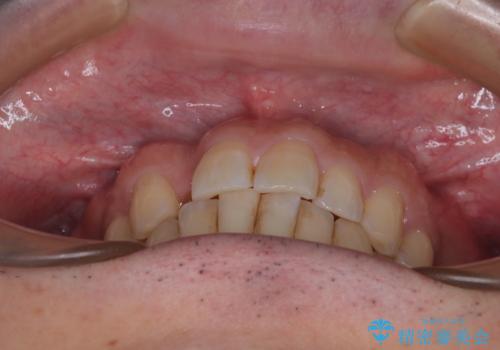

- 上下前歯のデコボコを気にして来院された患者様です。

ワイヤー矯正でもマウスピース矯正でも可能でしたが、短期間で、自身の手を煩わせることなく治療を行いたいとのことで、ワイヤー装置にて矯正治療を行うこととしました。

上顎前歯の舌側転位が顕著であったため、治療期間が長くなると思われましたが、僅か1年で無事に終えることができました。